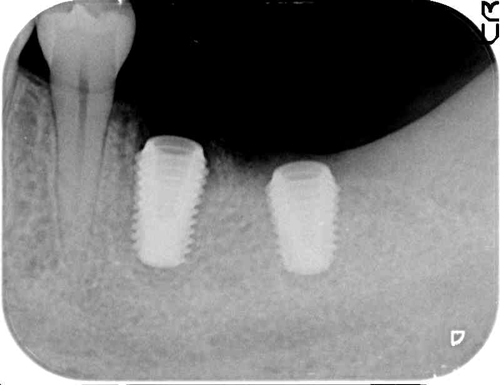

左下のレントゲン。

施術より3ヶ月後、インプラント完成。

右上のレントゲン。

施術から3ヶ月後、インプラント完成。